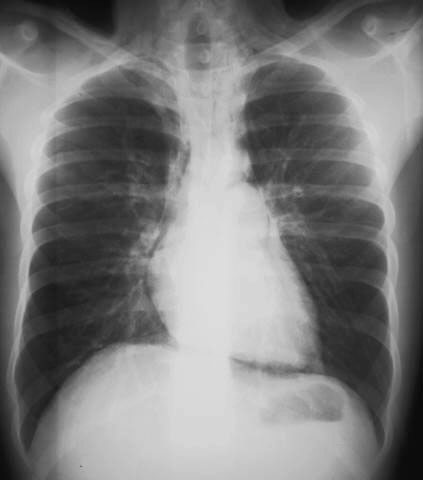

En la parte anterior del tórax son visibles los dos hemidiafragmas.

Signo de neumomediastino en la radiografía lateral de tórax, equivalente al signo del diafragma continuo en la placa anteroposterior o posteroanterior. En condiciones normales, el tercio anterior del hemidiafragma izquierdo está borrado porque el corazón hace silueta con él. En el neumomediastino, el gas entra entre el diafragma y el pericardio y permite ver el hemidiafragma izquierdo completo desde el seno costofrénico anterior hasta el posterior. Este hemidiafragma se reconoce por la disposición de la burbuja gástrica. En la imagen el hemidiafragfma derecho es el superior y el izquierdo el inferior.